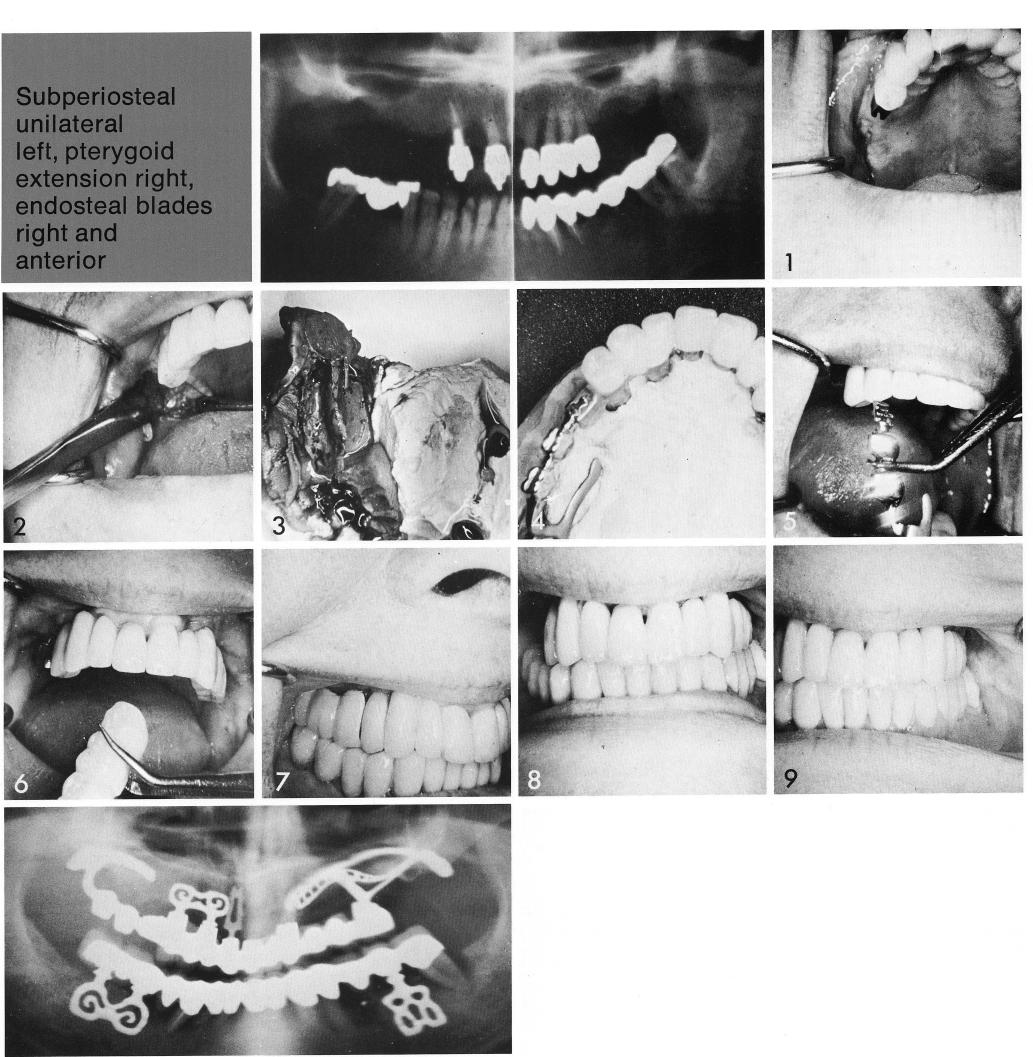

Subperiosteal unilateral

left, pterygoid

extension right,

endosteal blades

right and

Here a unilateral pterygoid extension implant was added to a three year old, implant supported restoration to re-place a right failing shallow bladevent. The restoration was divided and the remaining segment fitted with a female attachment (1). The site was exposed (2) for an impression (3) for the fabrication of the unilateral pterygoid extension implant (4,5). The new splint was added to the restoration (6), and the new occlusion carefully checked (7-9).

1 Pterygoid extension implant added to implant supported restoration